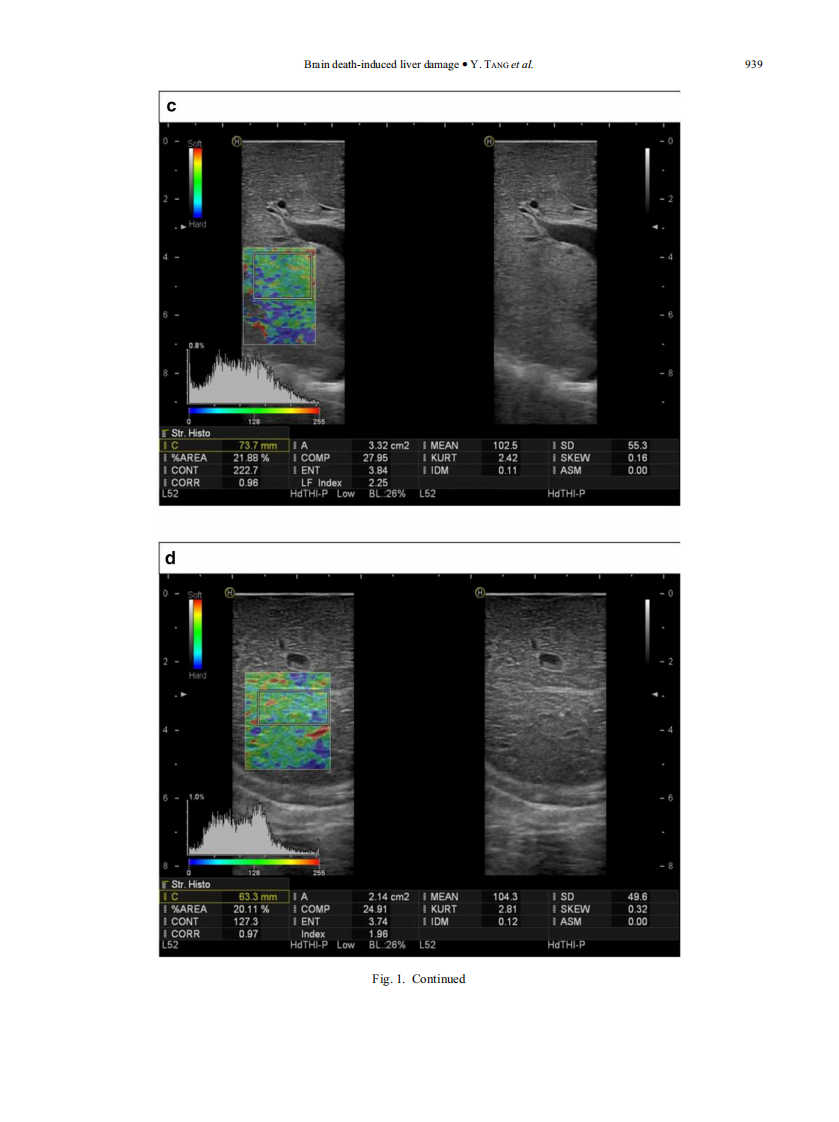

3)A comparison study of RTE and electron microscopy for assessment of liver damage.pdf

8)超声多模态评价猪脑死亡状态下肝脏损伤的实验研究.pdf